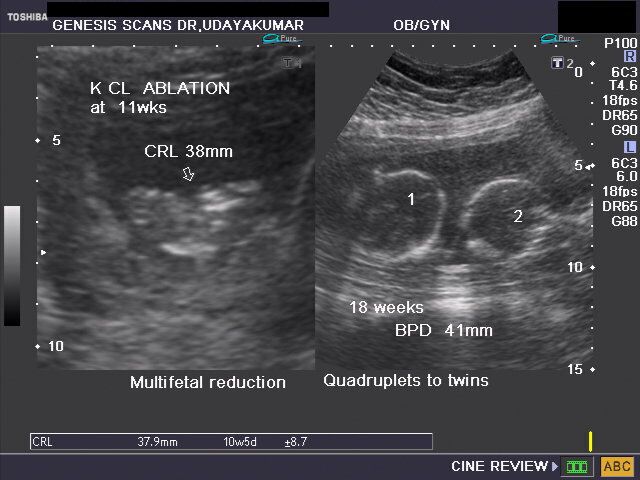

Multifetal reduction

The above ultrasound images reveal reduction of early quadruplet gestation by ablation (using KCl) of 2 fetuses, converting it successfully to a twin gestation (image on right half). Images courtesy of Dr. Udaya Kumar, Chennai, India.